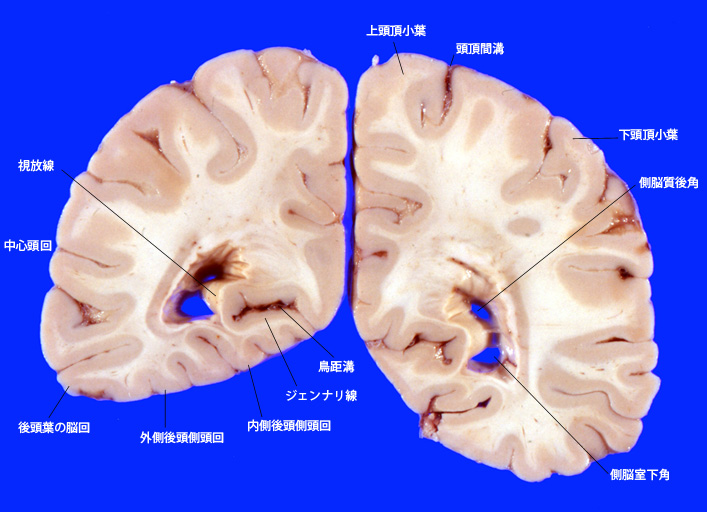

5. 後頭葉, 鳥距溝の断面